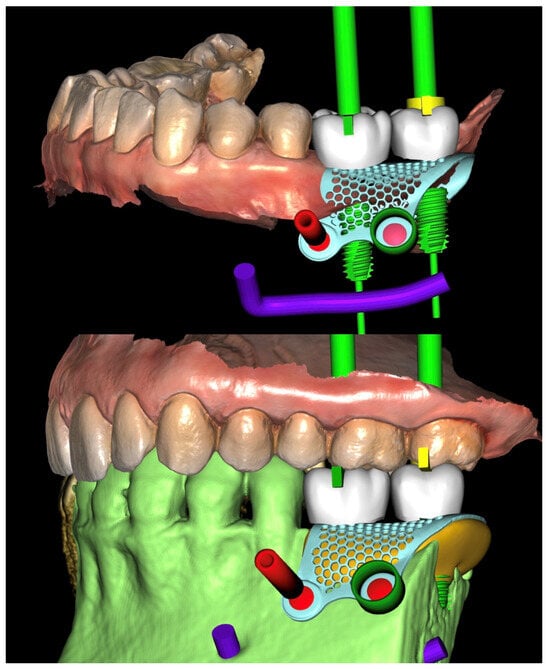

The virtual implant planning was exported and a customized CAD/CAM titanium mesh was designed based on a commercially available template (OssBuilder, Osstem Implant Co. Ltd., Seoul, Republic of Korea) (Figure 3).

Figure 3. Vertical guided bone regeneration (vGBR) procedure. The amount of bone graft (in yellow) was evaluated and considered according to the prosthetic design (in white). The titanium mesh was designed accordingly.

The mesh was designed by an expert using exocad (exocad’s PartialCAD 3.2 Elefsina, exocad GmbH, Darmstadt, Germany). and fabricated via laser melting (New Ancorvis Srl, Bargellino, Calderara di Reno, Italy). The maximum three-dimensional measures of the preplanned bone to be regenerated were 8.1 mm in height, 9.8 mm in width, and 19.6 mm in length, resulting in an estimated total volume of approximately 1197.8 mm3 (equivalent to 1.2 cm3). This volumetric estimation was derived from digital planning and served as a key parameter in guiding the grafting procedure and material selection.